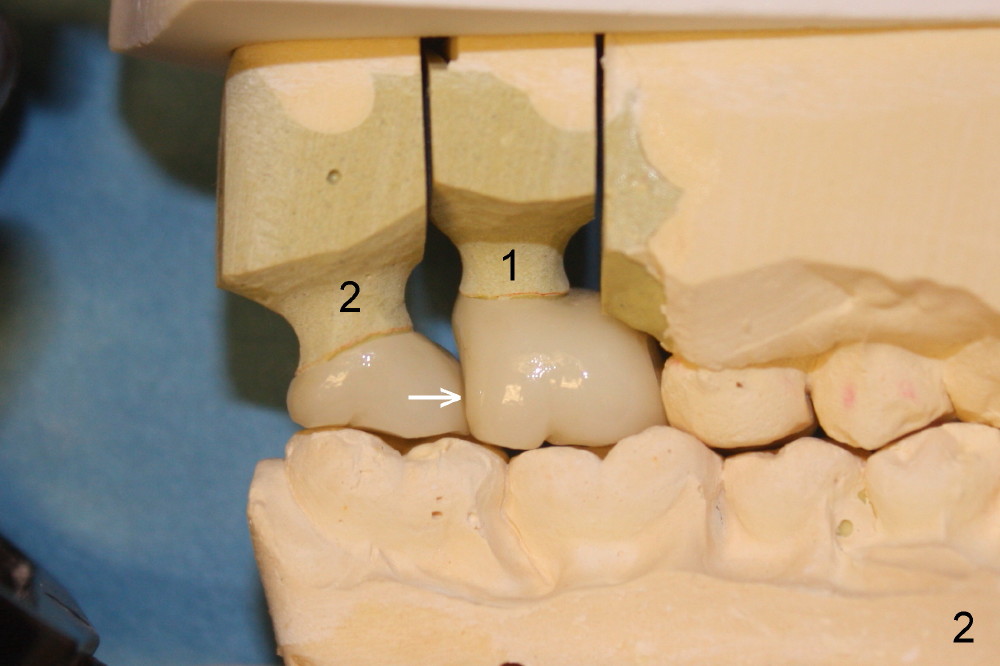

On the day of delivery, the model is studied (Fig.1 (buccal), 2 (lingual), 3 (occlusal)). The implant at the site of the1st molar (#1 in Fig.1-3) is placed distally; it is at the distobuccal cusp (DB in Fig.1). The crown of the 2nd molar (#2) has to extend mesially (Fig.2 arrow) for compensation. The buccolingual width of these two upper molar crowns is reduced, as evidenced by the edge to edge or mild cross bite of occlusal scheme (Fig.4). Anyway, it appears that the implant at the first molar is malpositioned. How to prevent it?